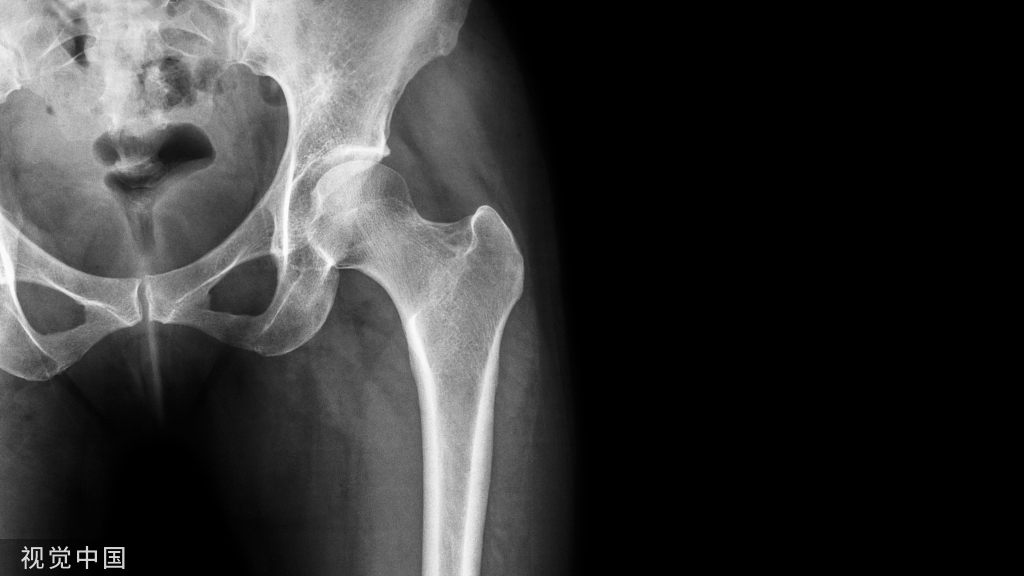

腰椎退行性病变是由椎间盘水分减少和弹性丧失造成,并且会导致腰疼或下肢疼痛、麻木等症状。通常采用理疗、镇痛和抗炎药物治疗等保守治疗,经过长期保守治疗无效的腰椎退行性病变常需要手术治疗,大量研究表明腰椎融合技术是治疗该病的标准术式。腰椎融合技术可以消除疼痛、减压神经根和固定手术节段,但在长期随访中,它会带来加速邻近节段退变、假关节形成等众多并发症。

为了解决这些问题,腰椎非融合技术应运而生,其目的是维持手术节段脊柱生理功能固有的稳定性,降低邻近节段退变发生率。近年来,腰椎非融合技术进展迅速,Wallis动态稳定系统作为腰椎非融合技术中的一种手术方式,它不仅保留了手术节段固有活动度,而且解决了邻近节段退变等问题。但Wallis动态稳定系统的禁忌证与术后并发症不容忽视,并且适应证和远期的临床疗效仍存在争议。本文主要就Wallis动态稳定系统治疗腰椎退行性疾病的最新进展做一综述。